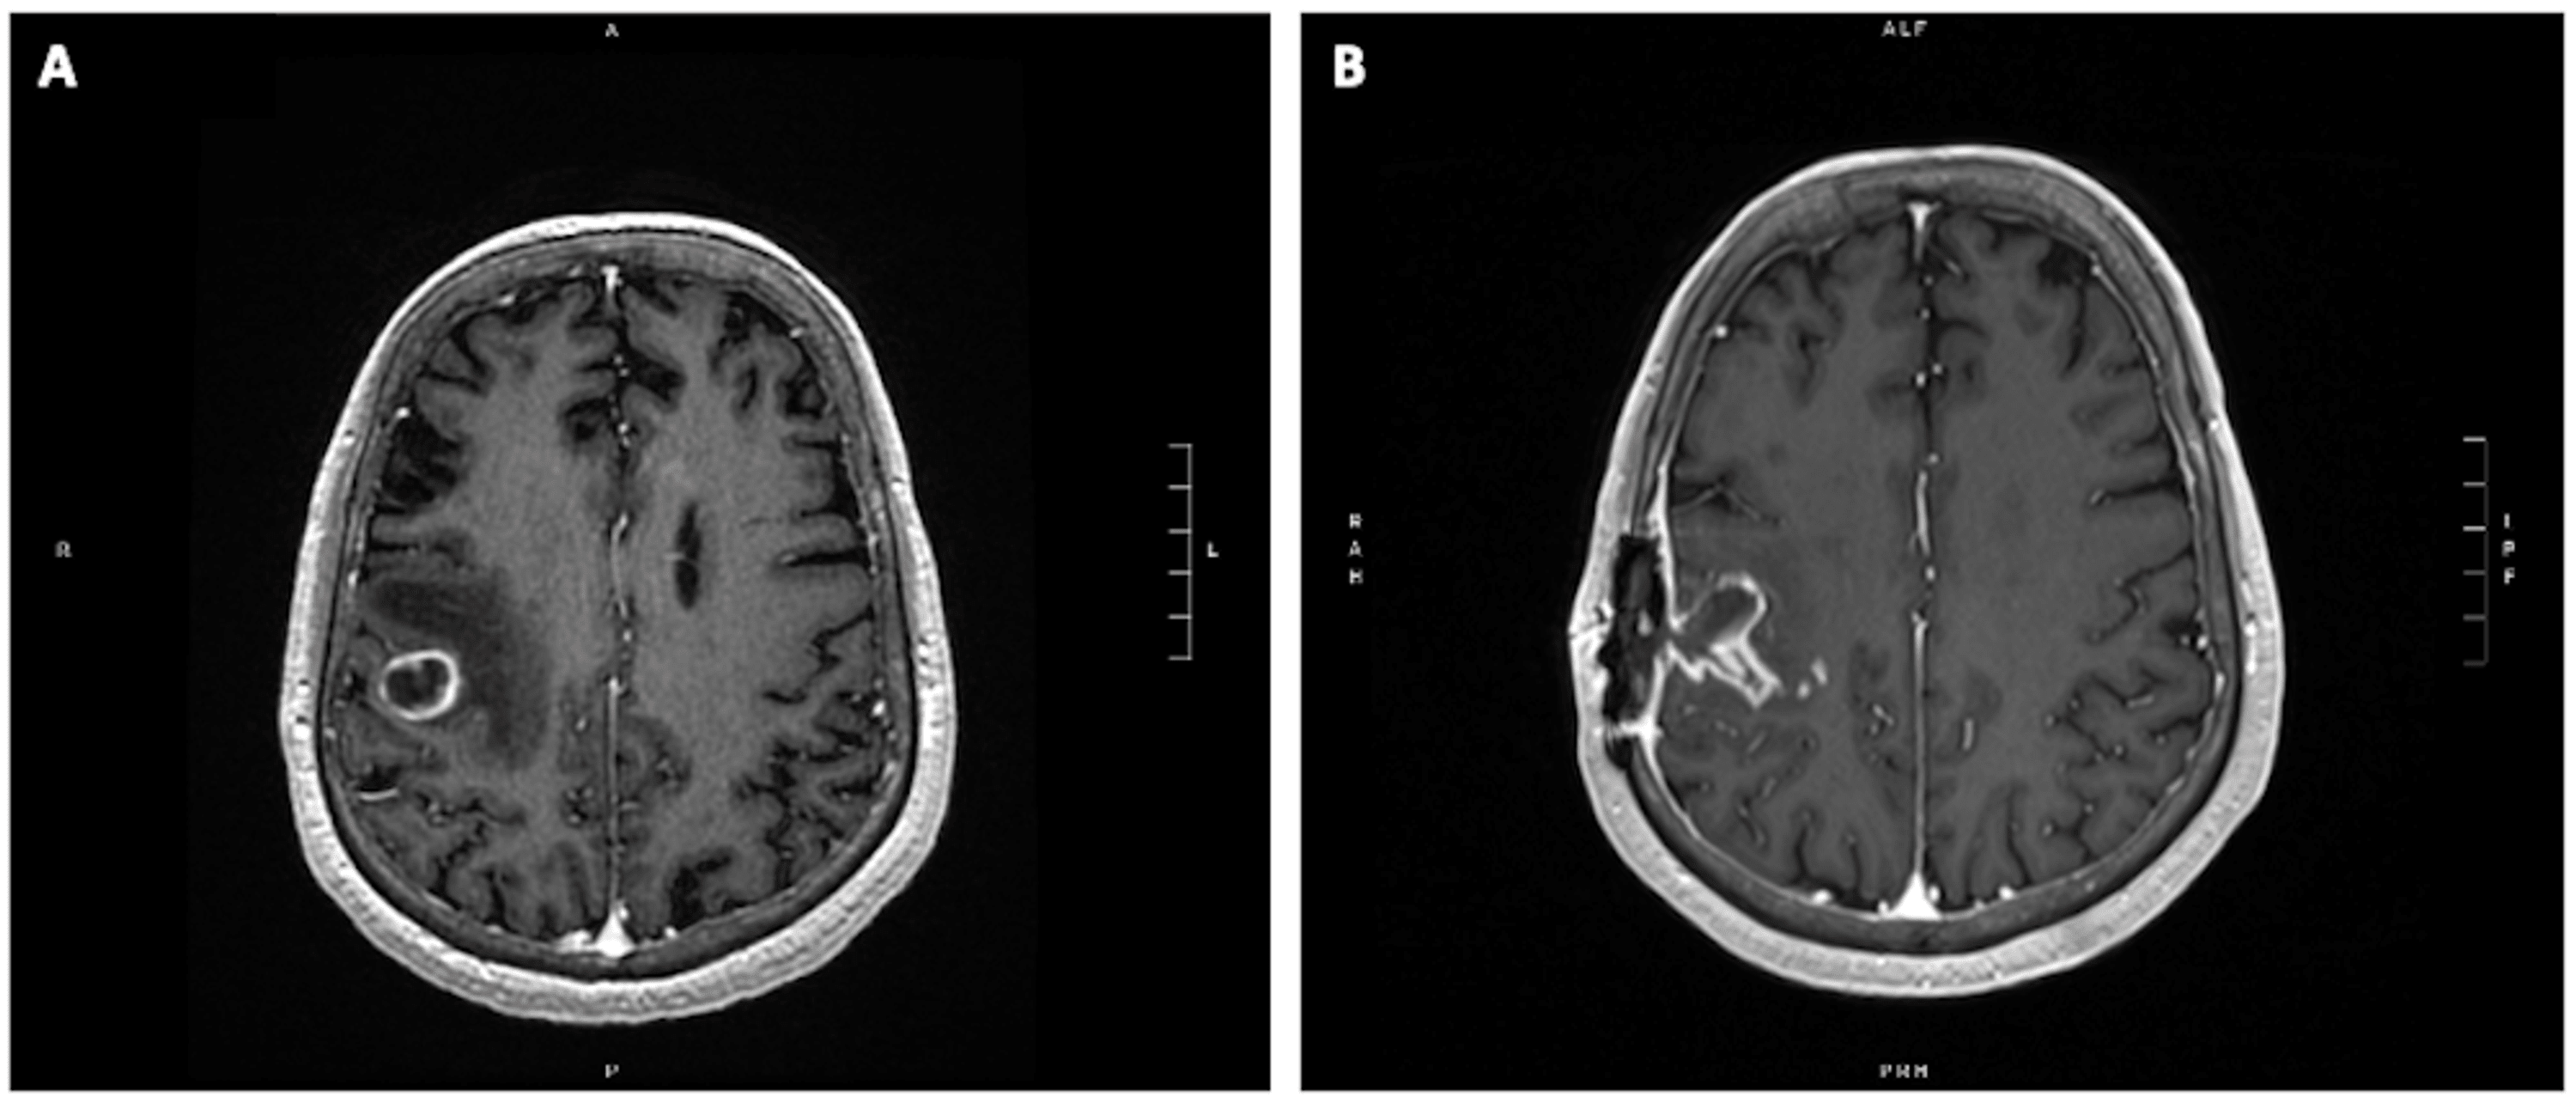

Example of brain metastasis treated with a second of radiosurgery Radiosurgery Brain Metastases If there are limited additional brain metastases, srs is recommended over wbrt. While whole brain radiation therapy. for patients with asymptomatic brain metastases and no systemic therapy options, stereotactic radiosurgery (srs) alone should be. stereotactic radiosurgery (srs) has become the standard of care for limited brain metastases to defer toxicities associated with whole. radiation therapy is commonly. Radiosurgery Brain Metastases.